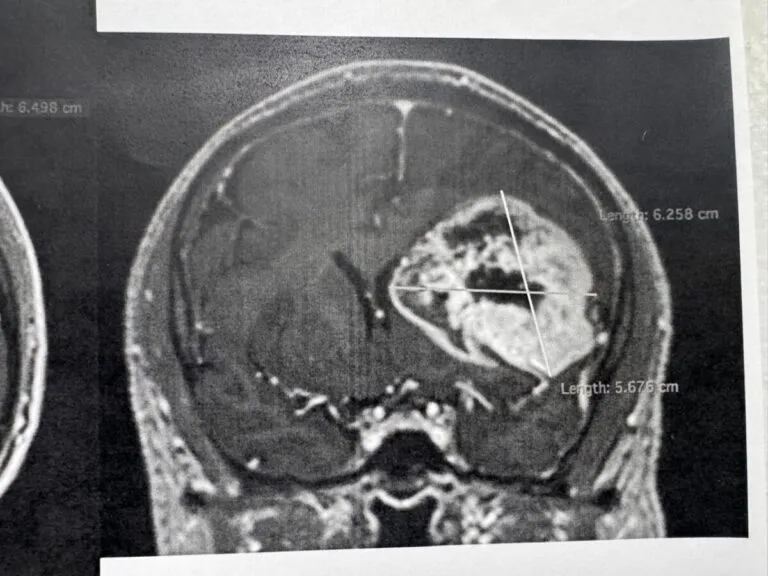

Retiran tumor cerebral con técnica de paciente despierto

Especialistas en neurología y de diversas áreas retiraron exitosamente un tumor cerebral a un derechohabiente...